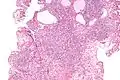

| Micrograph of a nephrogenic adenoma. H&E stain. | |

Nephrogenic adenomas are diagnosed under the microscope by pathologists. Microscopically the tumor shows closely packed small tubular structures in edematous stroma. The tubules show considerable variation in size and shape resembling convoluted tubules of the kidney. The single layer of cells lining the tubules are cuboidal with a scant to moderate amount of cytoplasm. In some areas they may have a hobnail appearance. [2]

Low mag